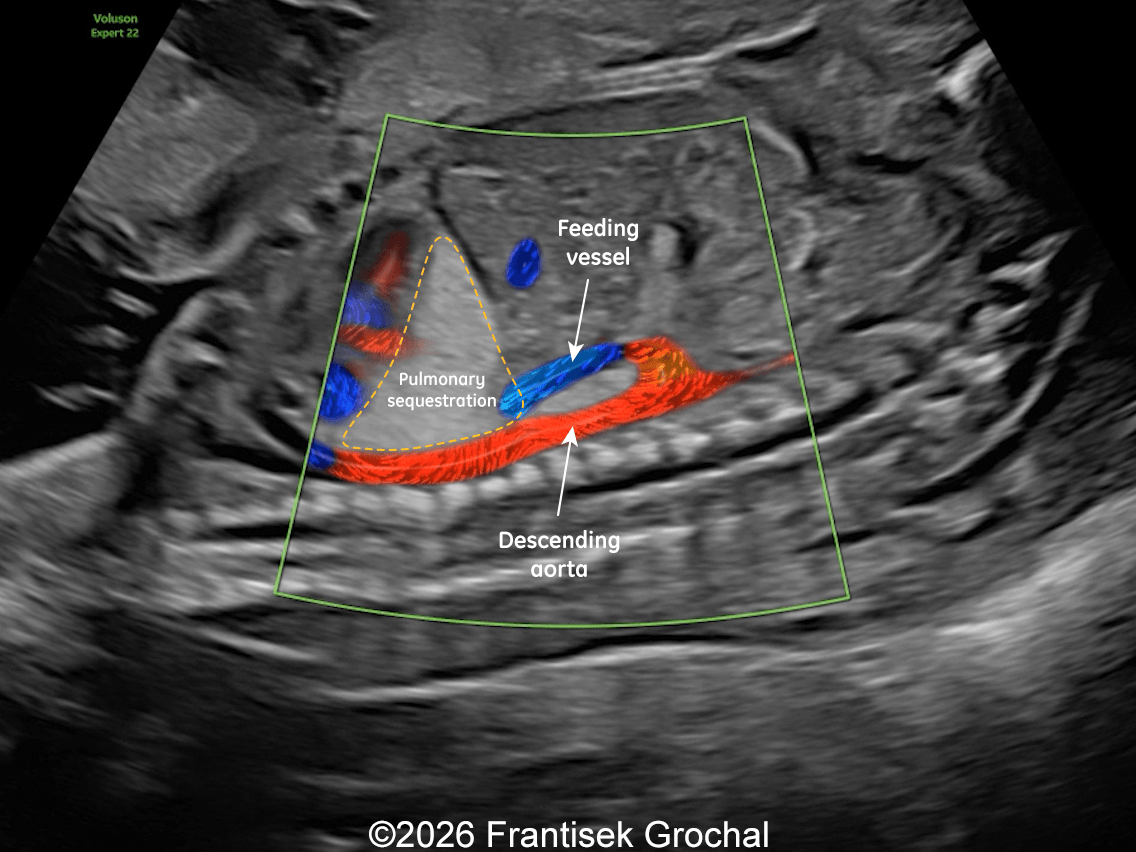

31+4 weeks – sagittal view demonstrating reduced size of the pulmonary sequestration with a small hypoechoic area within the lesion; color Doppler imaging still demonstrates a systemic feeding artery arising from the descending abdominal aorta.

Image 4 31+4 weeks – sagittal view demonstrating reduced size of the pulmonary sequestration with a small hypoechoic area within the lesion; color Doppler imaging still demonstrates a systemic feeding artery arising from the descending abdominal aorta.